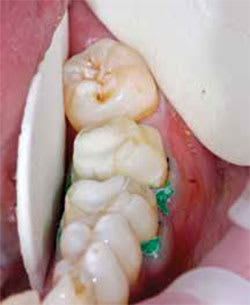

Figure 3 Case 1, isolated and ready to scan. | Figure 4 Case 1, scan view. | ||||||

In both cases, the author followed the same protocol used in conventional techniques to the point of completion of the preparations and placement of two retraction cords. The teeth to be scanned were then isolated with an OptraGate® (Ivoclar Vivadent, https://www.ivoclarvivadent.com) and dry angles. A very light application of titanium dioxide powder was placed per manufacturer to enable the Lava C.O.S. to record points of reflectivity. As with VPS impressions, dryness is essential. In each case, full-arch scans of both the operative quadrant and opposing arches were accomplished (Figure 1, 2, 3, 4, 5, 6).

Scanning with the Lava C.O.S. is considerably different than impressioning. The operator focuses on the computer monitor to ensure complete data capture. This is a learned skill; repetition will generate confidence and improve technique. The scanner records the interocclusal relation with the patient in maximal intercuspal position and displays the articulated case on the monitor. A touch screen enables the operator to view the scans from every angle. After a review of the scans, the electronic prescriptions were completed and all data captured was transmitted via wireless router to the authorized design laboratory for completion of virtual articulator selection, digital margin marking, digital die trimming, SLA model manufacture, and CAD/CAM or traditional restoration fabrication.